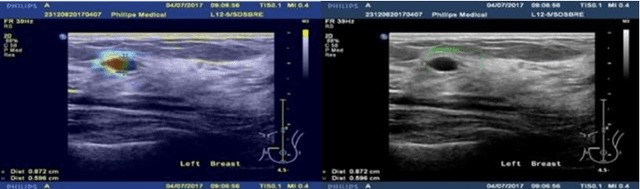

Abstract:This paper focuses on the classification task of breast ultrasound images and researches on the reliability measurement of classification results. We proposed a dual-channel evaluation framework based on the proposed inference reliability and predictive reliability scores. For the inference reliability evaluation, human-aligned and doctor-agreed inference rationales based on the improved feature attribution algorithm SP-RISA are gracefully applied. Uncertainty quantification is used to evaluate the predictive reliability via the Test Time Enhancement. The effectiveness of this reliability evaluation framework has been verified on our breast ultrasound clinical dataset YBUS, and its robustness is verified on the public dataset BUSI. The expected calibration errors on both datasets are significantly lower than traditional evaluation methods, which proves the effectiveness of our proposed reliability measurement.

Abstract:Objective: Breast cancer screening is of great significance in contemporary women's health prevention. The existing machines embedded in the AI system do not reach the accuracy that clinicians hope. How to make intelligent systems more reliable is a common problem. Methods: 1) Ultrasound image super-resolution: the SRGAN super-resolution network reduces the unclearness of ultrasound images caused by the device itself and improves the accuracy and generalization of the detection model. 2) In response to the needs of medical images, we have improved the YOLOv4 and the CenterNet models. 3) Multi-AI model: based on the respective advantages of different AI models, we employ two AI models to determine clinical resuls cross validation. And we accept the same results and refuses others. Results: 1) With the help of the super-resolution model, the YOLOv4 model and the CenterNet model both increased the mAP score by 9.6% and 13.8%. 2) Two methods for transforming the target model into a classification model are proposed. And the unified output is in a specified format to facilitate the call of the molti-AI model. 3) In the classification evaluation experiment, concatenated by the YOLOv4 model (sensitivity 57.73%, specificity 90.08%) and the CenterNet model (sensitivity 62.64%, specificity 92.54%), the multi-AI model will refuse to make judgments on 23.55% of the input data. Correspondingly, the performance has been greatly improved to 95.91% for the sensitivity and 96.02% for the specificity. Conclusion: Our work makes the AI model more reliable in medical image diagnosis. Significance: 1) The proposed method makes the target detection model more suitable for diagnosing breast ultrasound images. 2) It provides a new idea for artificial intelligence in medical diagnosis, which can more conveniently introduce target detection models from other fields to serve medical lesion screening.